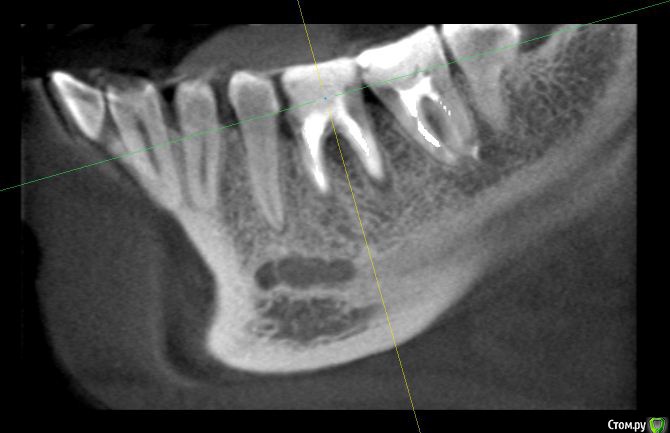

alex_ts Опубликовано 7 ноября, 2016 Поделиться Опубликовано 7 ноября, 2016 (изменено) Здравствуйте. Периодически беспокоит нижняя 6ка, 3 года назад она была на 3/4 разрушена и там стояла "металлическая" черная пломба, от которой зуб приобрел синий оттенок. На мой вопрос что его наверное надо удалять, стоматолог на меня тогда удивленно посмотрела и сказала что корни хорошие и ничего удалять не надо. Тогда же она поставила очень большую пломбу, сказав что это не на долго и так или иначе придется одевать коронку. Сейчас зуб время от времени побаливает и иногда кровит. Сходил в клинику, сделали кт зуба. Врач сказала что варианта 2, либо долго и сложно лечить этот зуб и протезировать, но без гарантии, так как там затемнение в области фуркации, либо удалять и ставить имплант. Что вы порекомендуете в данной ситуации? Спасать зуб или лучше будет избавиться от него? Мч, 24 года Изменено 7 ноября, 2016 пользователем alex_ts Ссылка на комментарий

anvladd Опубликовано 7 ноября, 2016 Поделиться Опубликовано 7 ноября, 2016 Лучше удалить,разрушен между корнями. 2 Ссылка на комментарий

DmitrySH Опубликовано 7 ноября, 2016 Поделиться Опубликовано 7 ноября, 2016 Плохой прогноз для лечения, удалять 2 Ссылка на комментарий